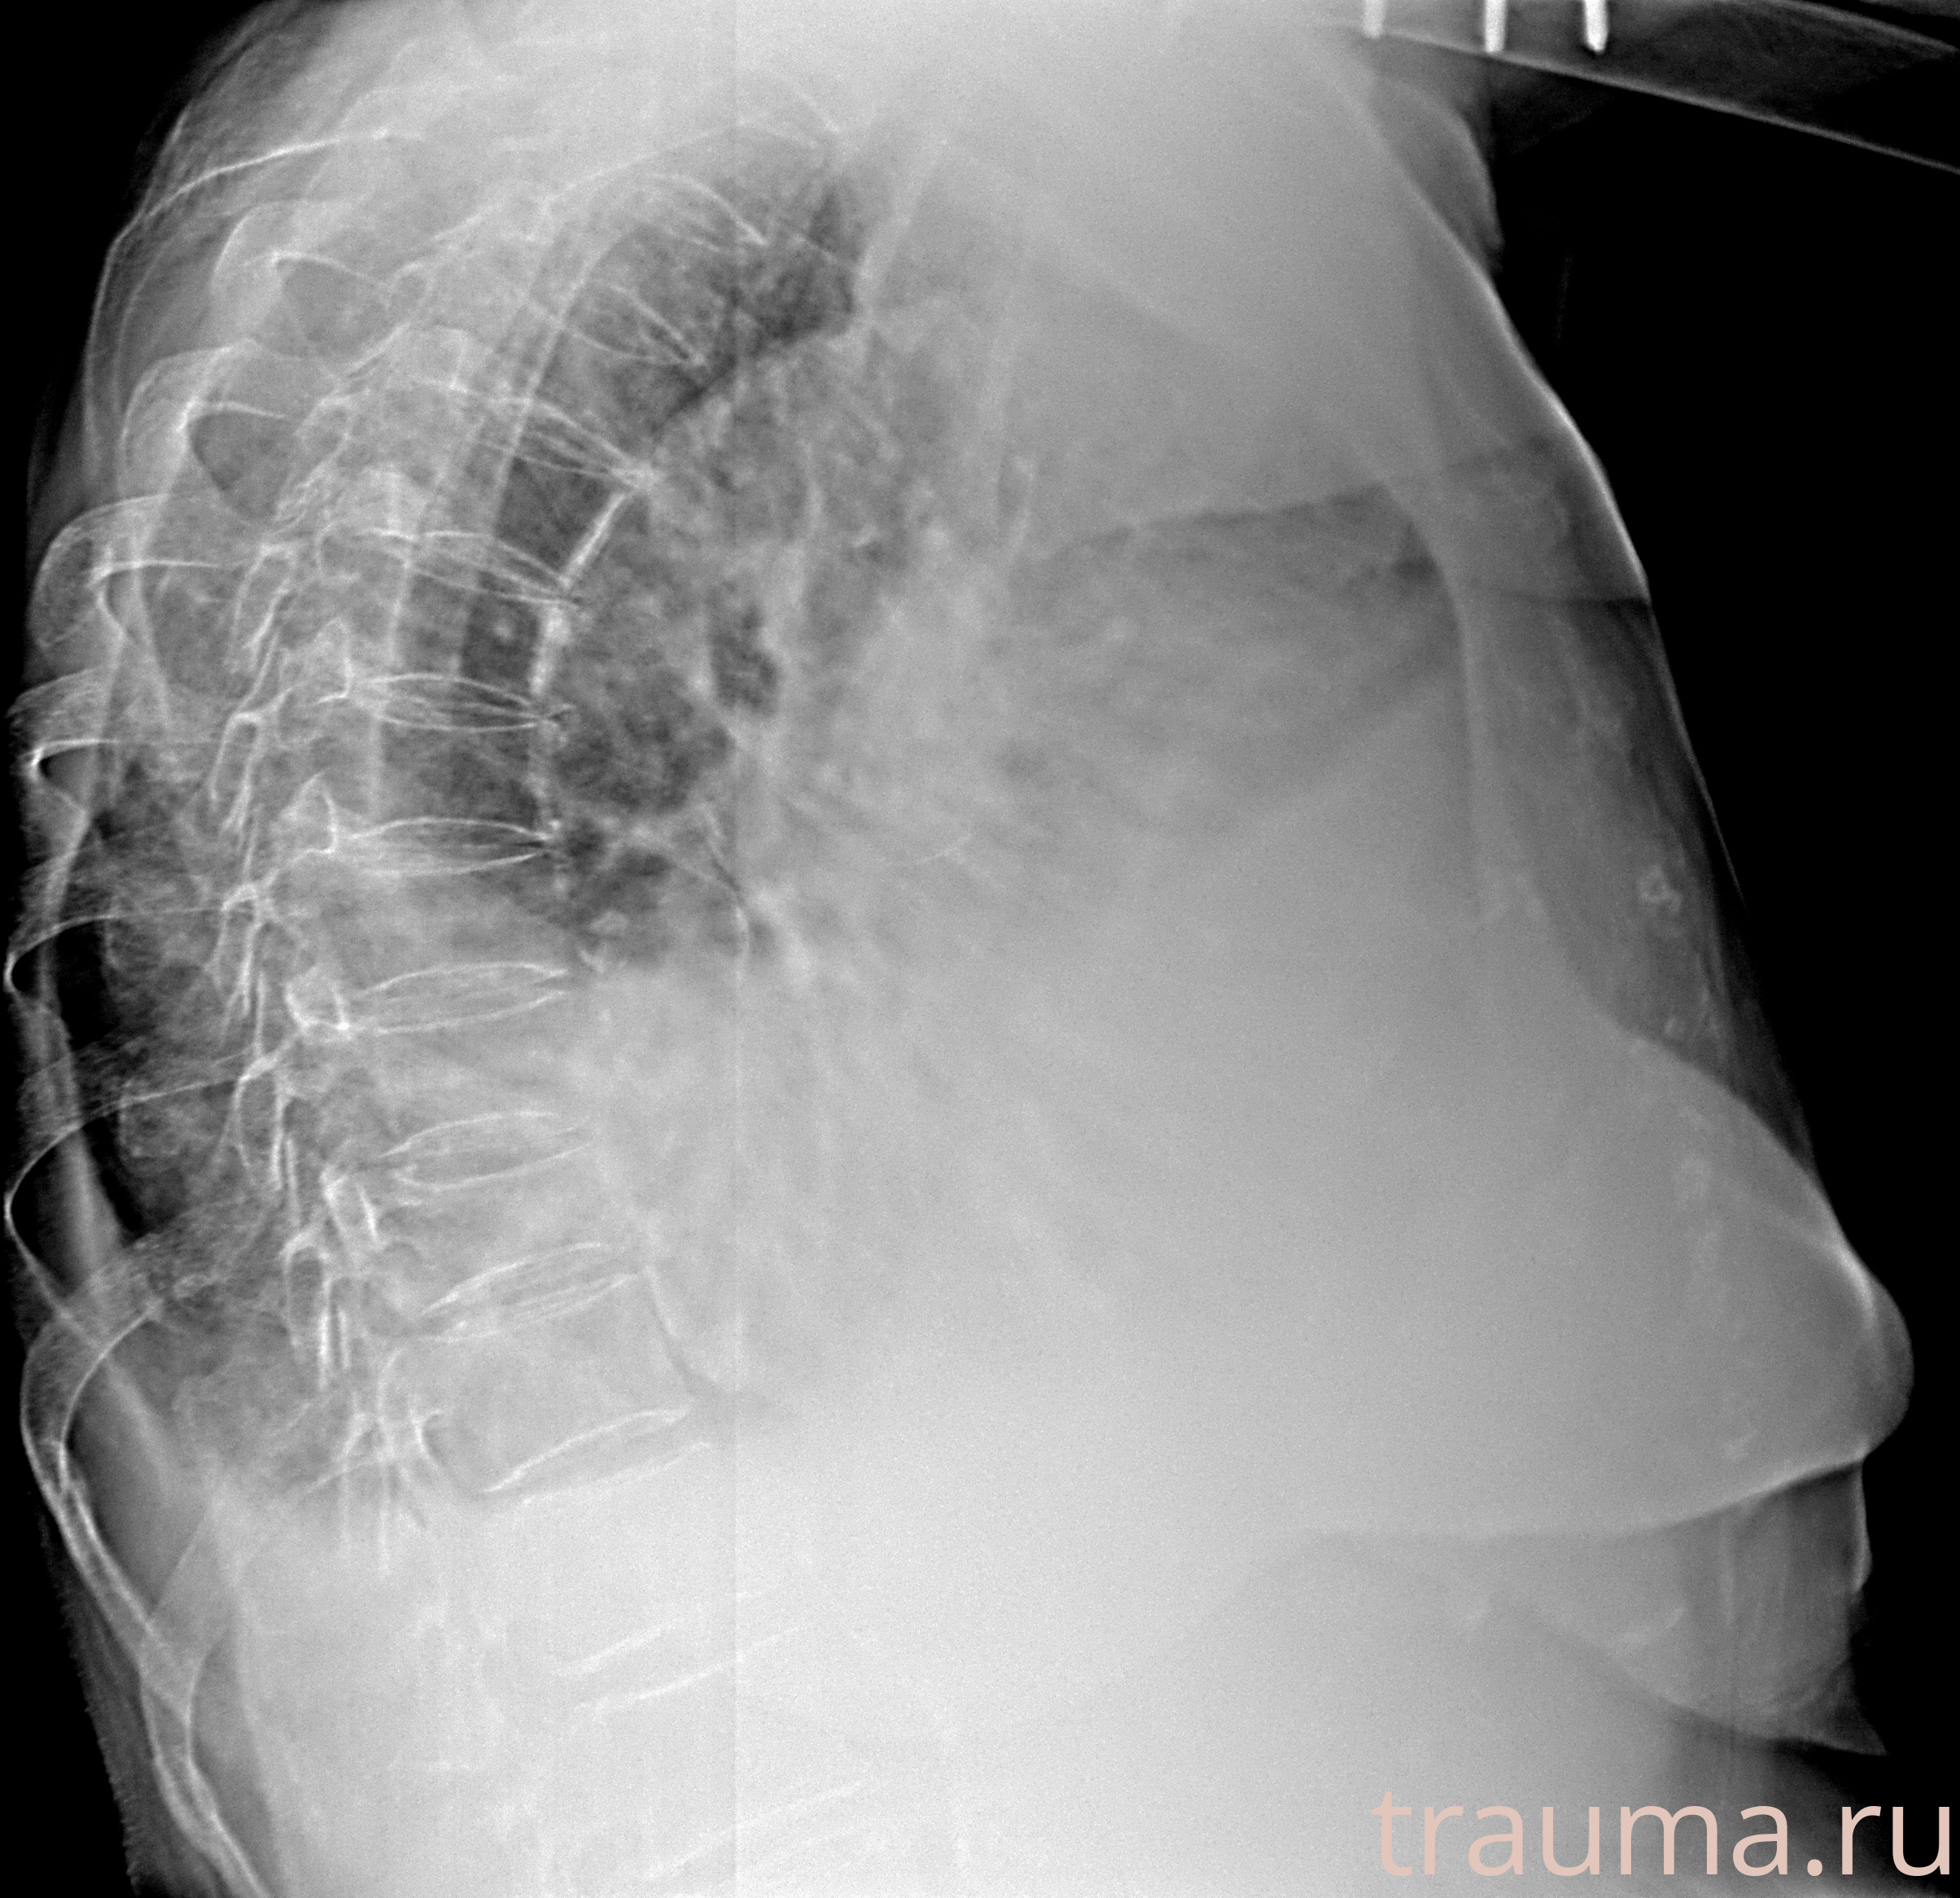

Рентген на дому: по вашему адресу приезжает врач-рентгенолог, травматолог-ортопед с мобильным рентгеновским аппаратом, проводит диагностику травмы или заболевания, делает необходимые рентгенограммы, дает рекомендации по дальнейшему лечению. Получить качественные снимки в домашних условиях возможно благодаря уникальной методике, разработанной МосРентген Центром для института  Склифосовского

при переломе шейки бедра и пневмонии от компании МосРентген Центр - партнера Института имени Склифосовского